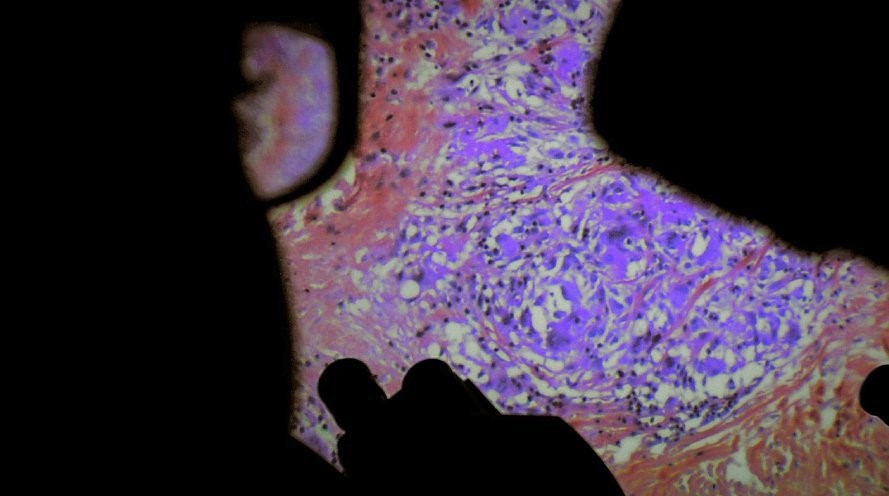

"In their thrilling new work of nonfiction exploration, Véréna Paravel and Lucien Castaing-Taylor, best known for such aesthetically and ethnographically revelatory films as Leviathan and Caniba, burrow deeper than ever, using microscopic cameras and specially designed recording devices to survey the wondrous landscape of the human body. More transfixing than clinical, the film, shot in hospitals in and around Paris, eschews the normal narrative parameters for medical documentation in favor of a rigorously detached, expressionistic look at our tactile yet essentially unknowable flesh and viscera. With its unshakable images of biopsies, cesarean delivery, endoscopic procedures, and the little-seen crevices inside all of us, De Humani Corporis Fabrica both demystifies and celebrates life and death." Film at Lincoln Center